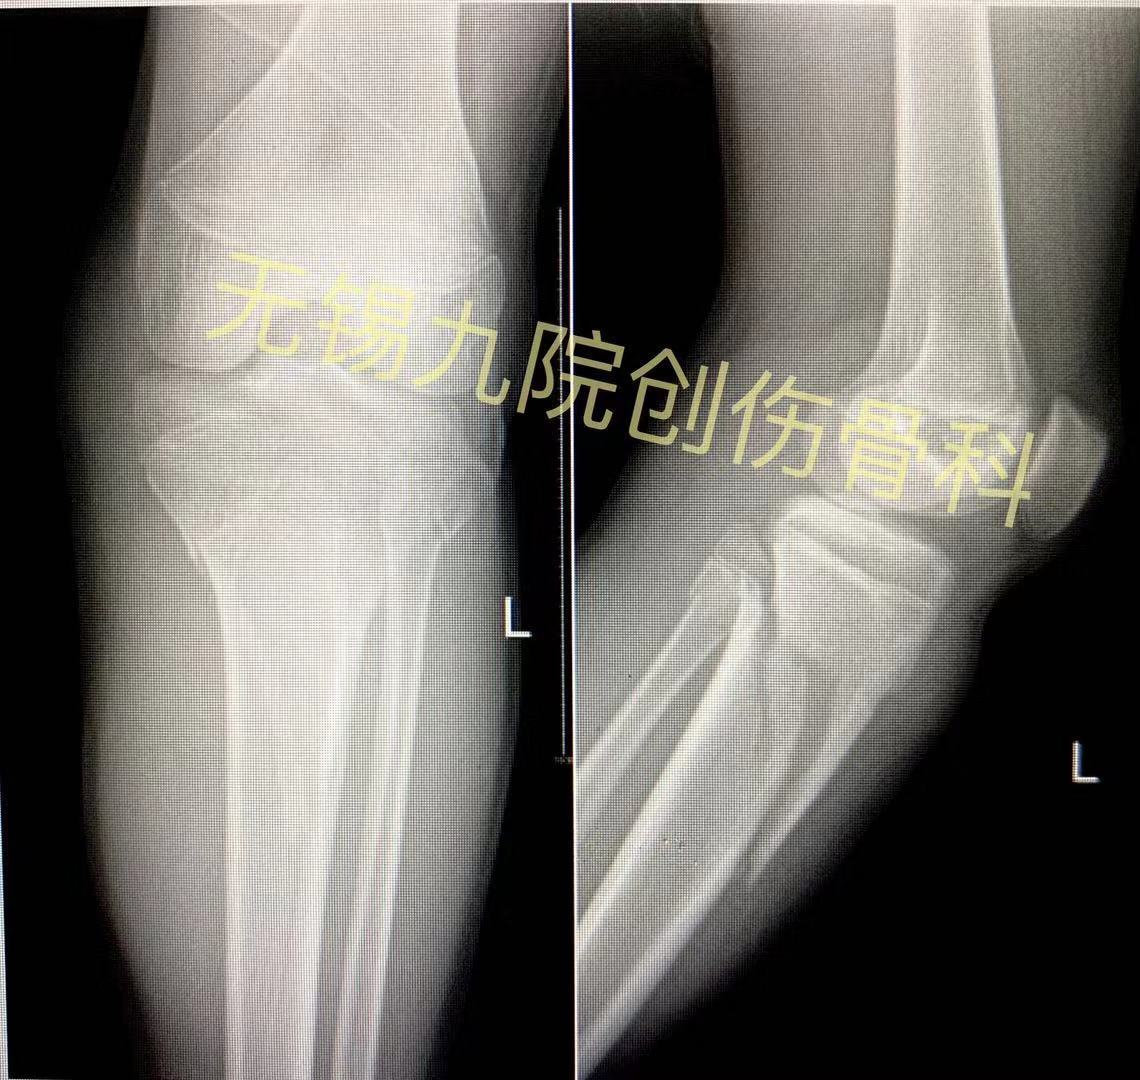

胫骨中段骨折最优内固定 髓内钉还是钢板 好医术早读文章 好医术 赋能医生守护生命

脛骨骨幹骨折 手術

脛骨骨幹骨折 手術-脛腓骨骨幹骨折症狀 1症狀 脛腓骨骨折多為外傷所致,如撞傷,壓傷,扭傷或高處墜落傷等,傷肢疼痛並出現腫脹,畸形等。 脛骨的位置表淺,局部症狀明顯,在重視骨折本身症狀的同時,還要重視軟組織 治療 脛骨遠位端骨折 (けいこつえんいたんこっせつ) では、その原因によってそれぞれ治療が異なります。 内果骨折 骨折部の偏位や脱臼による足関節の変形が著明でない場合には、ギプス固定などの保存的な治療を行います。 変形が著しい場合には、骨折部を整復してねじを刺入して変

脛骨近位部骨折の基礎知識 point 脛骨近位部骨折とは 脛骨はすねの骨です。膝に近い部分の脛骨の骨折を脛骨近位部骨折といいます。交通事故や転倒、スポーツによって起こり、高齢者に多く見られます。骨折すると痛みや腫れ、変形などが見られます。 脛骨骨折。 横山医院は、横浜市保土ヶ谷区にて患者さんが安心して在宅療養をおくれるように、かかりつけ医として、内科・整形外科・外来診療を始めとした訪問診療(往診)を提供しています。 骨幹部骨折とは脛骨の中間部(すね)の骨折で、交通保存的治療に失敗,複数箇所での骨折,多発 外傷,Gustilo1.2の開放骨折などが適応に なる.Gustilo3は創外固定が適応. 2. 骨近位骨幹部骨折 最初に変形がなくても,遅発性に過成長と相 まって,外反変形を生じることがある.50%の

脛骨骨幹骨折 手術のギャラリー